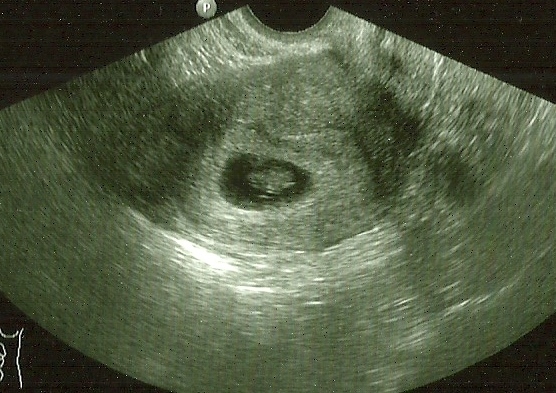

i've had to crop my scan, didn't think about the fact it had my full details on it... i'm totally blaming baby brain lol.

so, once again, here's baby booth :)